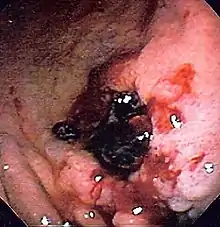

| Endoscopic image of a posterior wall duodenal ulcer with a clean base, which is a common cause of upper gastrointestinal hemorrhage. | |